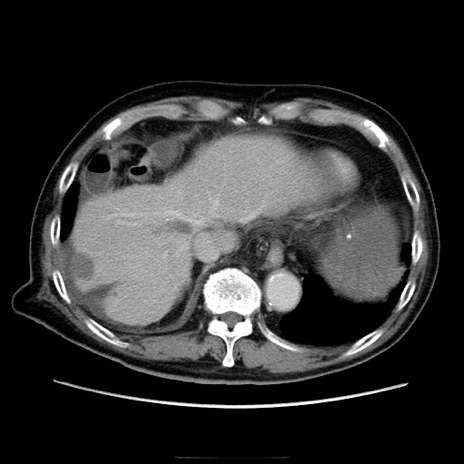

症例21(横断像)

【症例】70歳代男性

【主訴】腹痛

【現病歴】肝硬変・肝細胞癌にてかかりつけの方。約9時間前に食後より腹痛出現。症状が徐々に増悪し、嘔吐出現したため来院。

【既往歴】肝硬変、肝細胞癌(RFA、TACE後)

【身体所見】意識清明、表情苦悶様、BT 36℃、BP 129/78mmHg、P 88bpm、SpO2 97%(RA)、右上腹部から心窩部にかけて圧痛あり、反跳痛なし、筋性防御あり。

【データ】WBC 5800、CRP 0.16